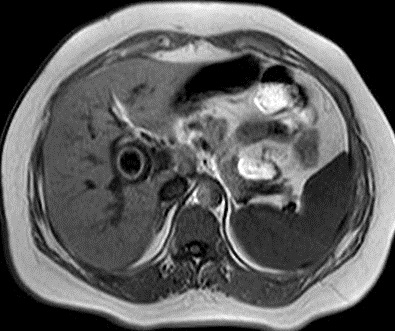

En coupe pondere sur T2 (

l'eau est hypersignal ) on peu en vue la vesicule

biliaire est distendue ,hyperintense tres net

et image de dilatation legere de voie biliaire

intra- hepatique |

Le calcul est en hyposignal

tres grand et arrondie en compressant le canal

hepatique commun . Image radiologique IRM pondere

sur T2 . |

Meme cas en coupe IRM a T2 coronal . La

vesicule biliaire est distendue et hyperintense . Le

calcul est en compessse sur la voie biliaire

principale . Le canal hepatique commun et voie

biliaire en amont est en leregement dilate . |